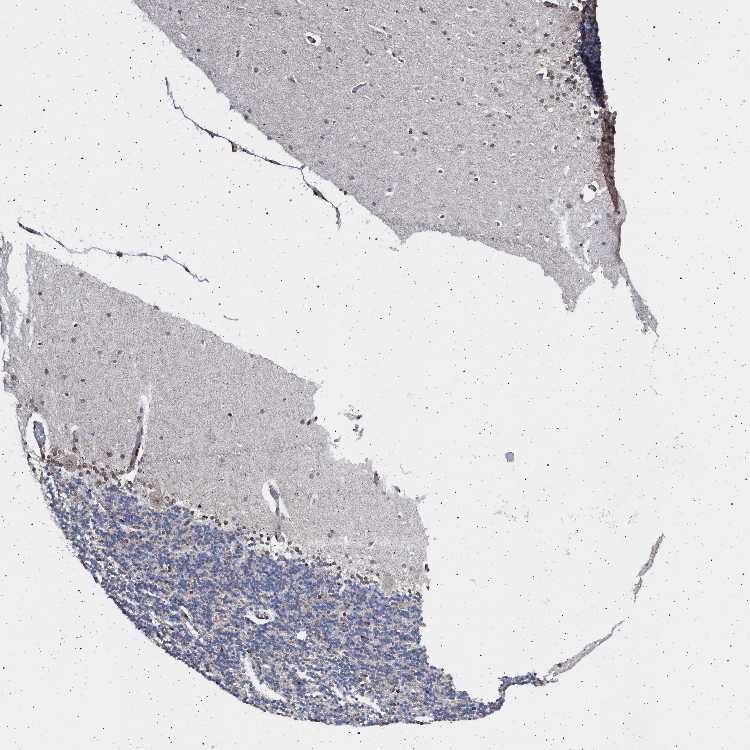

CEREBELLUM - Antibody stainingi

Antibody staining in the annotated cell types in the current human tissue is reported as not detected, low, medium, or high, based on conventional immunohistochemistry profiling in selected tissues. This score is based on the combination of the staining intensity and fraction of stained cells.

Each image is clickable and will lead to virtual microscopy that enables deeper exploration of all samples and also displays staining intensity scores, fraction scores and subcellular localization as well as patient and tissue information for each sample.

Antibody HPA019486Antibody HPA021517

Purkinje cells Not detectedMedium

Cells in granular layer LowLow

Cells in molecular layer HighLow